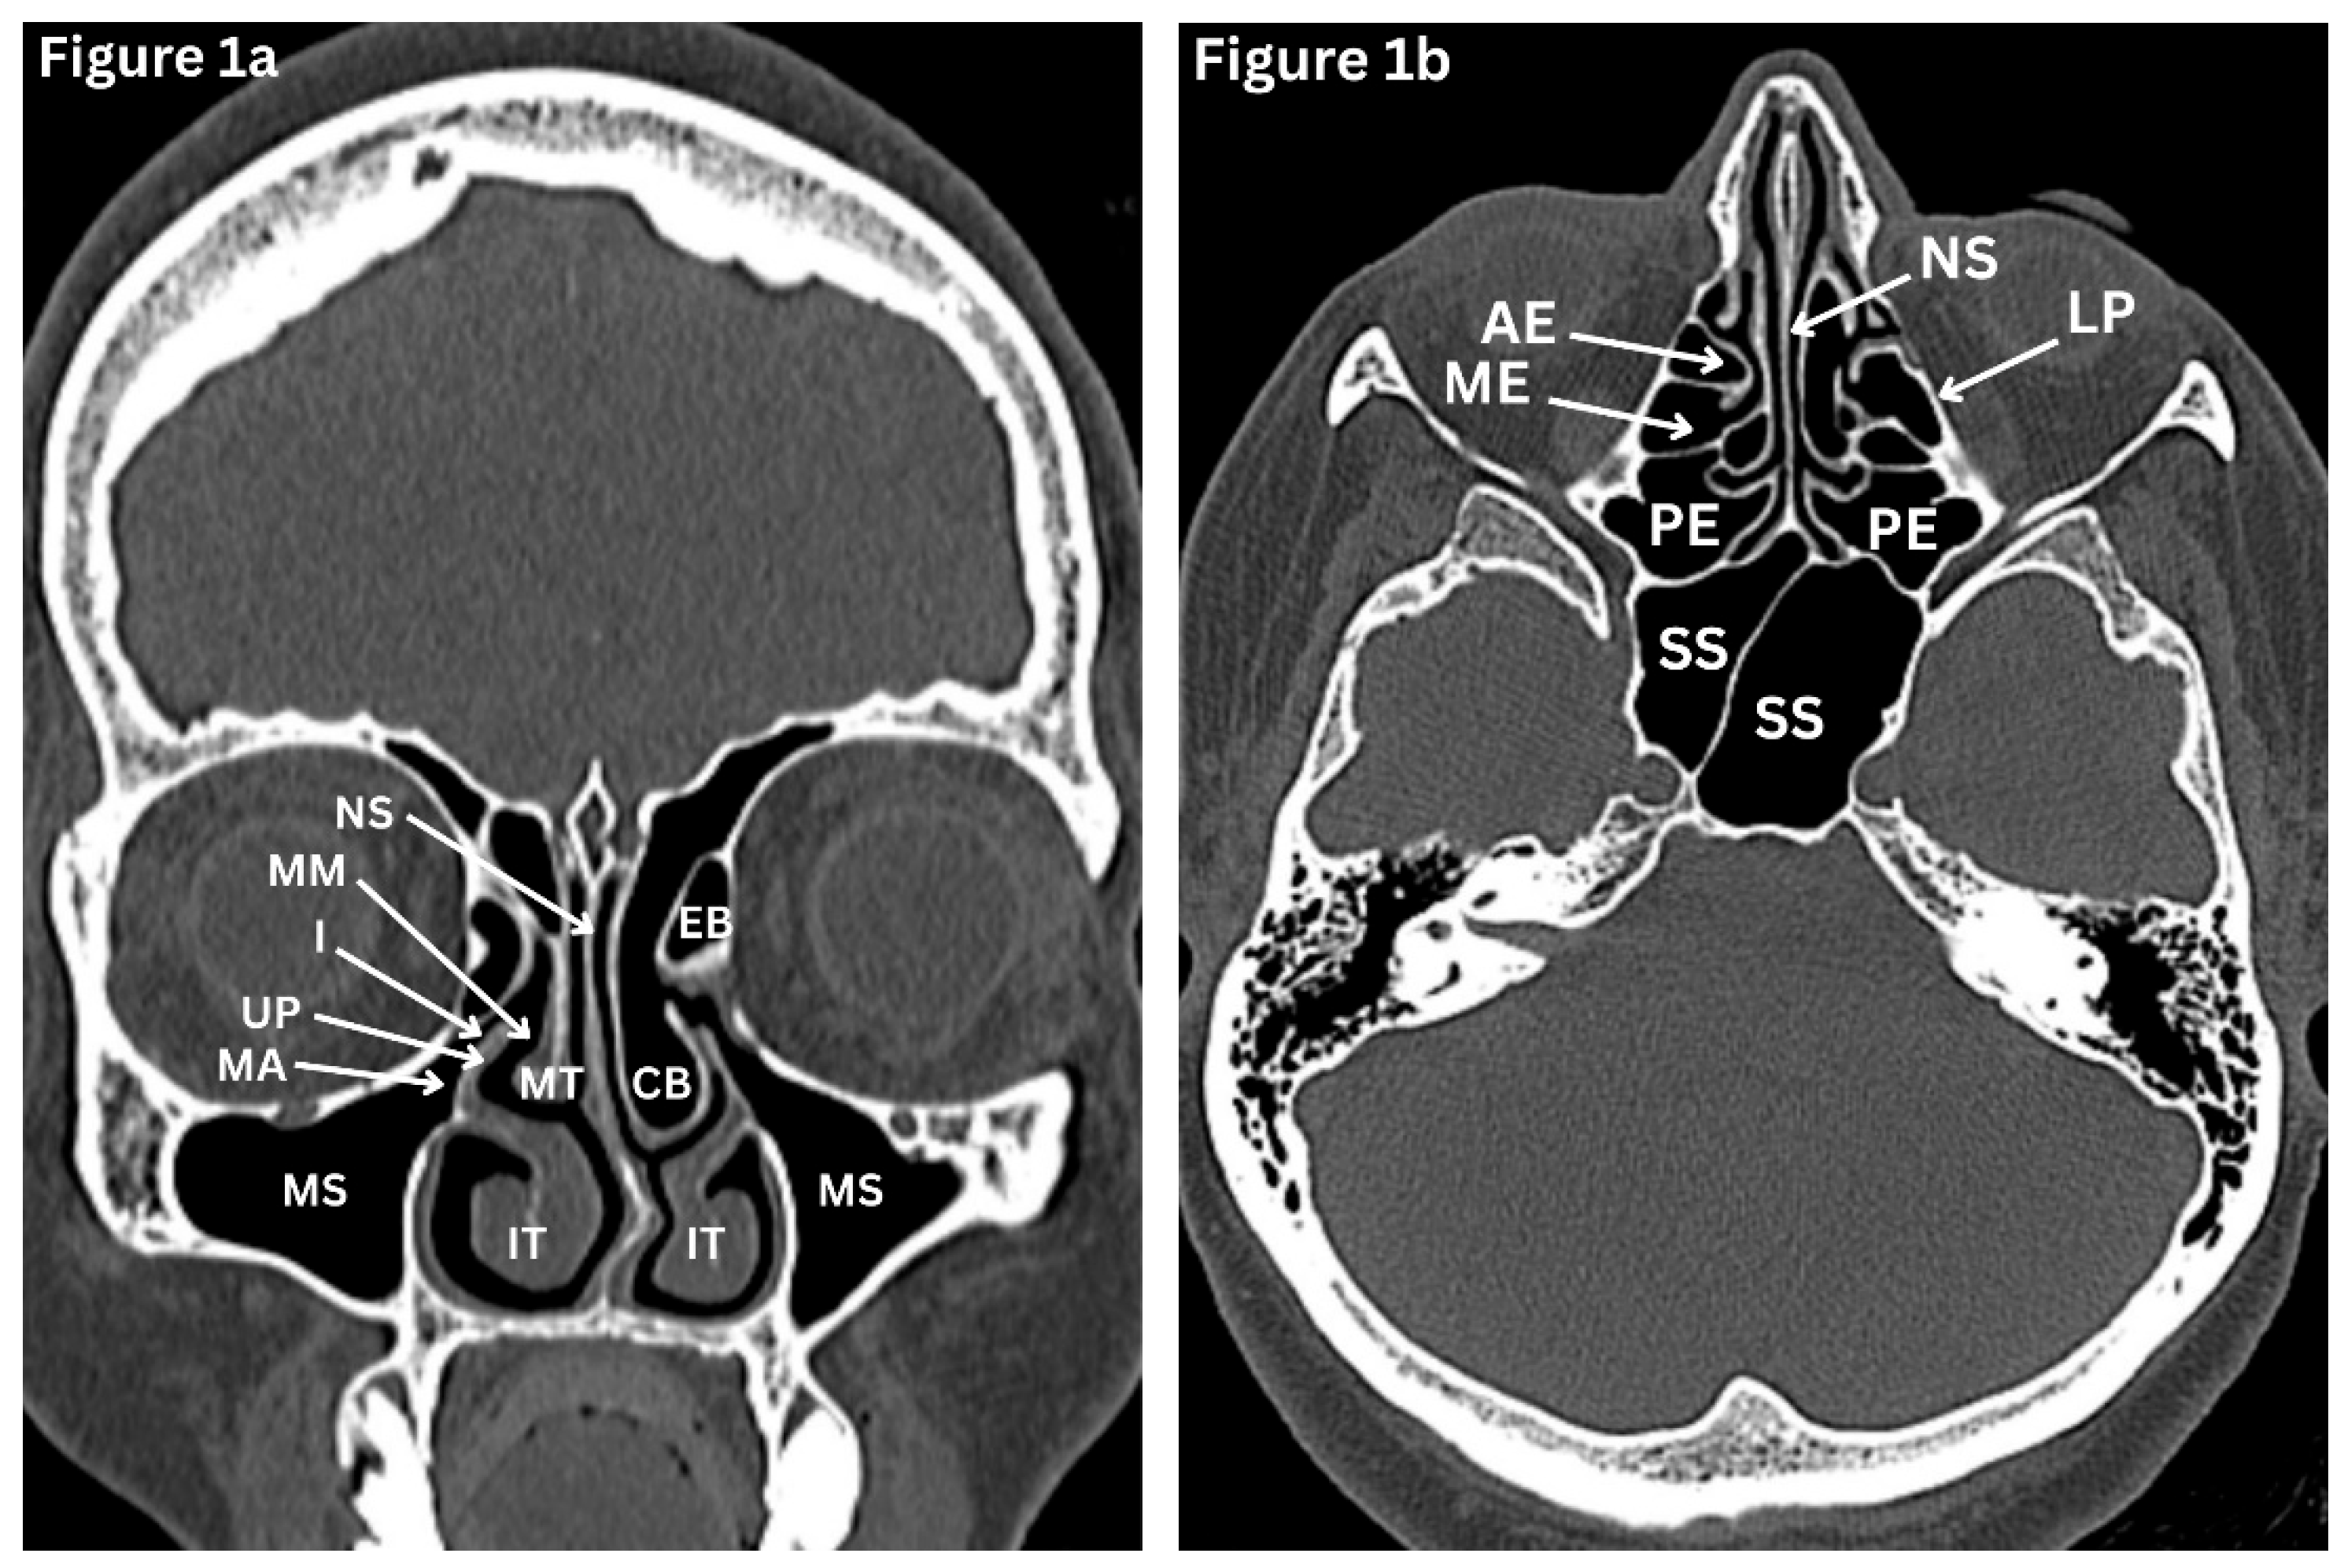

Figure 1. a-c: HRCT paranasal sinuses (bone window). a-Coronal; b-Axial; c-Sagittal images. NS: Nasal septum; MT: Middle turbinate; IT: Inferior turbinate; MM: Middle meatus. I: Infundibulum; UP: Uncinate process; MA: Maxillary antrum; MS: Maxillary sinus; AE: Anterior ethmoid sinus; ME: Middle ethmoid sinus; PE: Posterior ethmoid sinus; SS: Sphenoid sinus; FS: Frontal sinus; EB: Ethmoid bulla; CB: Concha bullosa; LP: Lamina papyracea; FR: Frontal recess; ANC: Agger nasi air cell; HF: Hypophyseal fossa.

The maxillary sinus is the largest of the paranasal sinuses, pyramidal in configuration, and the most frequently affected sinus in inflammatory disease. It is located within the body of the maxilla, with its medial wall forming the lateral boundary of the nasal cavity and its apex extending laterally into the zygomatic process. (Figure 1a) Inferiorly, the sinus floor is related to the alveolar part of the maxilla and lies in proximity to the roots of the premolar and molar teeth, with odontogenic communication reported in up to 40% of individuals [1]. This explains why dental infections may mimic or trigger sinus disease. Superiorly, the roof of the sinus contributes to the orbital floor and contains the infraorbital nerve, together with the superior alveolar branches of the maxillary nerve, which provide sensory innervation to the region. The maxillary sinus ostium is situated on the posterosuperior aspect of the medial wall. It drains into the middle meatus of the lateral nasal wall via the posterior part of the infundibulum. Because of this high, non-dependent position, effective drainage depends on intact mucociliary clearance rather than gravity. This anatomical configuration predisposes to secretion retention and recurrent maxillary sinusitis, particularly when mucosal oedema, anatomical variation, or obstruction of the ostiomeatal complex is present [1,2].

The ethmoid labyrinth contains multiple small air cells arranged in anterior, middle, and posterior groups. (Fiture1a-c) The number of ethmoid air cells varies between individuals, but they typically consist of about seven smaller anterior cells and four larger posterior cells. Their anatomical boundaries are clinically important. The anterior and middle cells drain into the middle meatus, while the posterior cells drain into the superior meatus. The ethmoid sinuses are separated from the orbit by the delicate, paper-thin lamina papyracea, making orbital complications of ethmoiditis potentially risky. Both nerve and blood supply arise from branches of the ophthalmic nerve and artery [1,2].